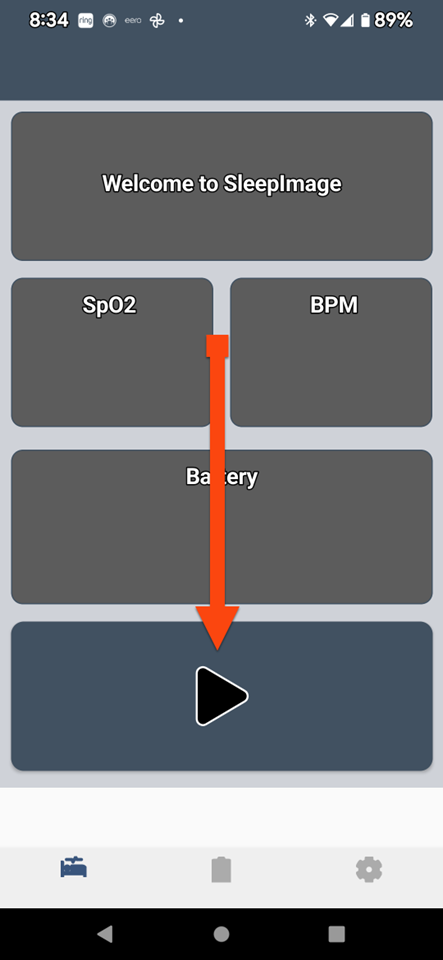

SLEEPIMAGE APP (Android)

SLEEPIMAGE APP (Android)

SLEEPIMAGE APP (Android)

SLEEPIMAGE APP (Android)

SLEEPIMAGE APP (Android)

SLEEPIMAGE APP (Android)

SLEEPIMAGE APP (Android)

SLEEPIMAGE APP (Android)

SLEEPIMAGE APP (Android)

SLEEPIMAGE APP (Android)

SLEEPIMAGE APP (Android)

SLEEPIMAGE APP (Android)

SLEEPIMAGE APP (Android)

SLEEPIMAGE APP (Android)

SLEEPIMAGE APP (Android)

SLEEPIMAGE APP (Android)

SLEEPIMAGE APP (Android)

SLEEPIMAGE APP (Android)

SLEEPIMAGE APP (Android)

SLEEPIMAGE APP (Android)

SLEEPIMAGE APP (iPhone)

SLEEPIMAGE APP (Android)

SLEEPIMAGE APP (Android)

SLEEPIMAGE APP (Android)

SLEEPIMAGE APP (Android)

SLEEPIMAGE APP (Android)

SLEEPIMAGE APP (Android)

SLEEPIMAGE APP (Android)

SLEEPIMAGE APP (Android)